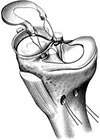

Nei casi in cui i sintomi dolorosi persistono o nei casi previsti, le rotture meniscali sono trattate anch’esse artroscopicamente con ottimi risultati. Le lesioni più periferiche (nella cosiddetta “zona rossa”) hanno qualche chances di guarire e per questo motivo possono essere suturate (nei pazienti giovani). Le rotture più comuni, tuttavia, avvengono nella zona più interna, la meno vascolarizzata (“zona bianca”); non avendo possibilità di cicatrizzarsi, la parte del menisco rotta viene semplicemente asportata.

In casi estremamente selezionati e in pazienti giovani con richieste funzionali elevate, i trapianti di menisco possono avere una indicazione.